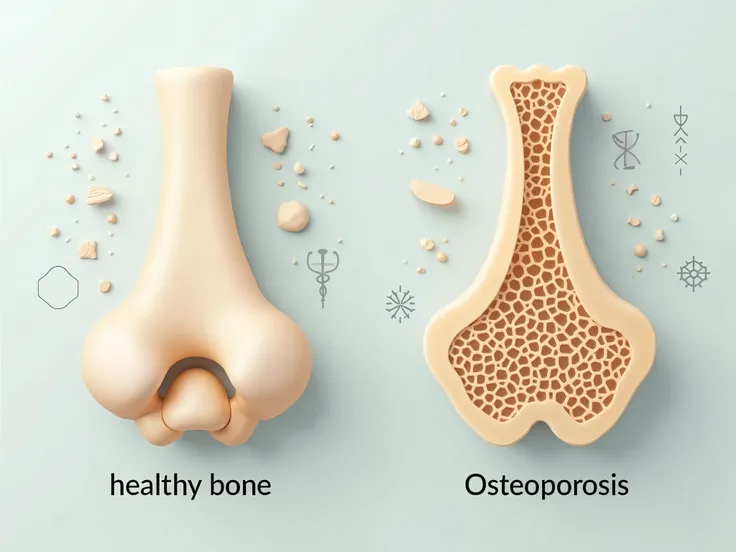

Close-up of human knee,There is a bone in the middle, knee, Knees, surreal bone structure, Protruding bones, Realphotos, orthographic view, Look across the shoulder, medical depiction, Osteoarticular joints, computer generated, hyper realisitc, sharp bone structure, joint, digital painted

surreal bone structure

Protruding bones

medical depiction

Osteoarticular joints

hyper realisitc

sharp bone structure